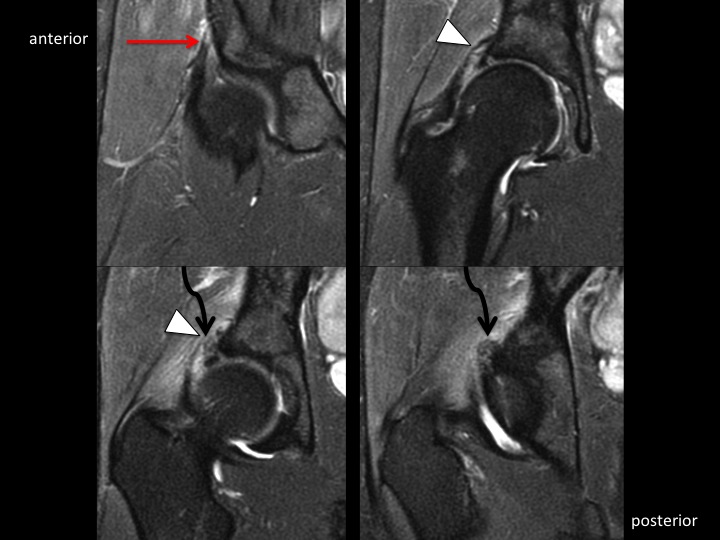

26F dancer with acute injury and hip pain

Yellow and Red arrows indicate partial tears at the origin of the direct and indirect head of the rectus femoris, respectively. The white arrowheads show acetabular stripping of the indirect head and iliofemoral ligament. I presume, due to the acuity of injury, that the dark amorphous signal (curved black arrow) is hemorrhage....but can I know that with certainty without either XR or US? I often have difficulty, particularly in shoulder, when I think there might be punctate calcific deposits that are unlikely to be visible by XR: would you recommend US in all such cases? (and, btw, I dont think the labrum is normal, but doubt thats her main problem...I suspect this will all heal with rest)